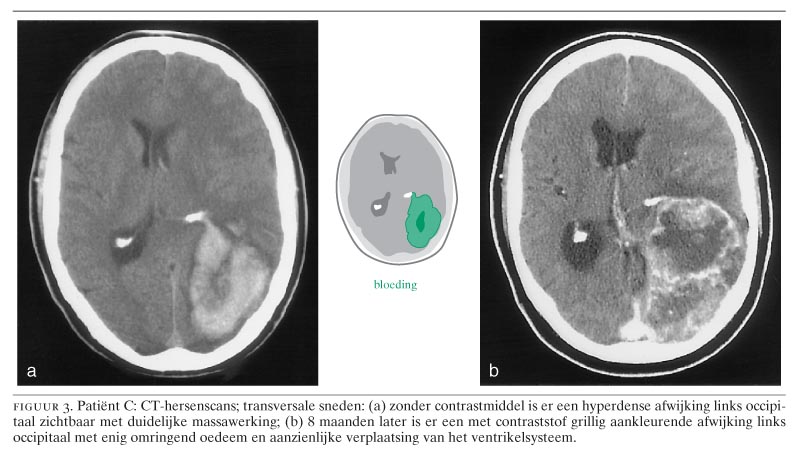

Patiënt C is een 53-jarige middenstander met in de voorgeschiedenis diabetes mellitus, waarvoor hij insuline spuit. Op familiebezoek kreeg hij plotseling last van misselijkheid en braken en verloor hij het bewustzijn. Patiënt werd in coma in het lokale ziekenhuis opgenomen. Op de CT-hersenscan werd links occipitaal een hyperdense afwijking gezien, passend bij een lobaire bloeding (figuur 3a). Omdat een vaatmalformatie werd vermoed, werd angiografie verricht, die echter geen afwijkingen liet zien. Om de intracraniële druk te verlagen ontlastte de neurochirurg het hematoom en er werd een extraventriculaire drain geplaatst. Hierdoor kwam patiënt vlot tot bewustzijn. Afwijkende vaatstructuren of abnormaal hersenweefsel werden tijdens de operatie niet gezien. Na elders te zijn gerevalideerd hield de patiënt als enig restverschijnsel hemianopsie rechts en ging hij weer aan het werk. In de maanden daarna klaagde hij echter in toenemende mate over hoofdpijn, vooral 's ochtends. Bovendien ontstonden er problemen met denken en spreken en ging hij minder scherp zien met zwarte vlekken rechts in het gezichtsveld.

Bij neurologisch onderzoek 8 maanden na de eerste gebeurtenis, werden op de polikliniek Neurologie motorische dysfasie en volledige hemianopsie rechts geconstateerd. De CT-hersenscan liet een hypodense afwijking links occipitaal zien met omringend oedeem. De afwijking kleurde ringvormig aan met contrastmiddel en leek het meest op een hooggradig glioom (zie figuur 3b). Met dexamethason verdwenen de taalstoornis en de hoofdpijn. De neurochirurg verwijderde de afwijking, die bij pathologisch onderzoek een glioblastoma multiforme bleek te zijn, macroscopisch volledig. Postoperatief was de patiënt in een goede neurologische conditie en hij werd uitwendig bestraald. Tot op heden zijn er geen tekenen van recidieftumorgroei.